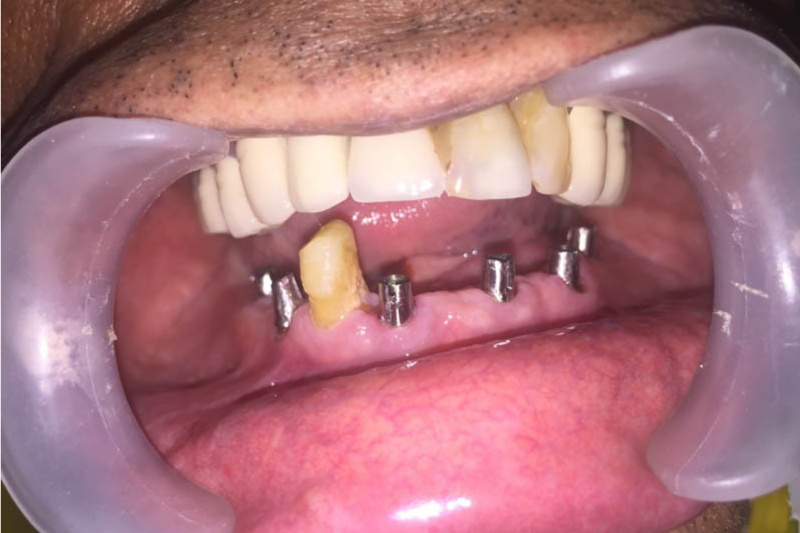

All on 4 All On 6 Implants

All on 4 or all on 6 treatment concepts is a graft less solution that provides patient with a fixed full arched prosthesis on the day of the surgery.

This treatment concept was developed to maximize the use of available remnant bone in atrophic jaws, allowing immediate function and avoiding regenerative procedures that increase the treatment costs and patient morbidity, as well as the complications inherent to these procedures

Advantage – graft less solution, immediate form and function, life changing, scientifically proven, very high success rate